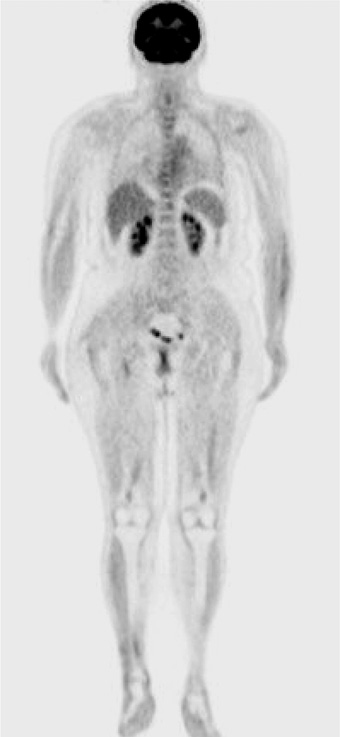

При обследовании (КТ органов грудной клетки, органов брюшной полости и таза с внутривенным контрастированием – в/в) подтверждено множественное метастатическое поражение печени, селезенки, лимфоузлов средостения, практически всех отделов костной системы (рис. 4, 5), при этом уровень ЛДГ оставался в норме, а общее состояние по шкале Восточной объединенной онкологической группы (Eastern Cooperative Oncology Group) соответствовало 1 за счет симптомов заболевания. Мтс в головном мозге по данным магнитно-резонансной томографии (МРТ) от 10.2015 не выявлены. При стадировании заболевания согласно Американскому объединенному онкологическому комитету (American Joint Committee on Cancer – AJCC) версии 7 – TxN0M1с, IV стадия; по AJCC версии 8 – TxN0M1с(0), IV стадия.

Рис. 4. КТ органов грудной клетки, органов брюшной полости и таза с в/в контрастированием от 10.2015.

Рис. 5. Радио-изотопное сканирование костей от 10.2015.